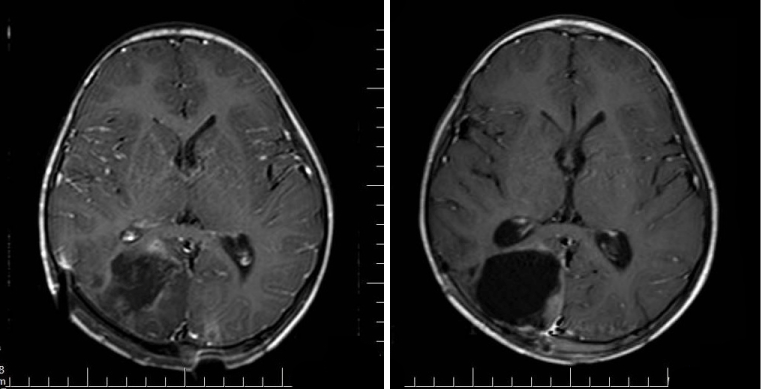

An 8-year-old boy who was living in countryside, was brought to ER because of vomiting due to head trauma. His neurological examination was normal. CT scan revealed a cystic lesion in right parieto-occipital region with approx. 5 cm diameter (Figure 1). By cranial MRI large cystic lesion with periferal enhancement was detected (Figure 2). Indirect hemagglutination was negative. Before surgery, 15 mg/kg/d albendazole treatment was administrated. Further examinations revealed no other involvement in body. Right parieto‑occipital craniotomy performed and lesion was totally excised. Post-operative recovery was uneventful. In pathological examination, fibrous wall was excised and smooth semi-transparent hydatid cyst was seen (Figure 3). Albendazole treatment was continued. Cranial MRI at the post-op 2nd month revealed no pathological findings (Figure 4).